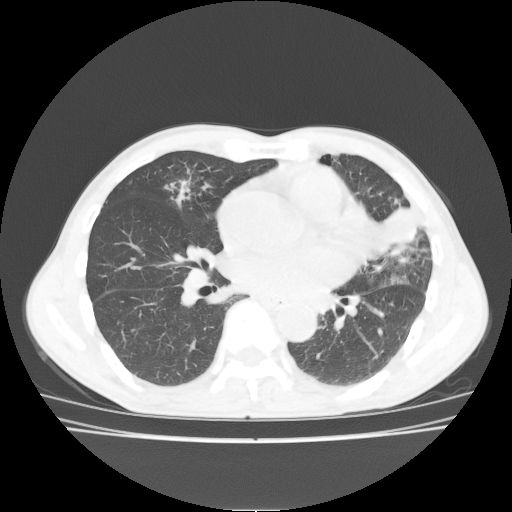

标题: CT25795:感冒后反复咳嗽两月余,痰中带血半月余。X诊断“肺 [打印本页]

标题: CT25795:感冒后反复咳嗽两月余,痰中带血半月余。X诊断“肺

1.双肺肺梗塞(理由:病灶呈三角形,与胸膜相连且局部胸膜肥厚,左心室增大)伴肺感染。

肺梗塞虽然有创意,但不现实。我考虑感染性病灶。

考虑两肺感染性病变,左肺上叶舌段肿瘤性病变待排;建议抗炎治疗后复查。